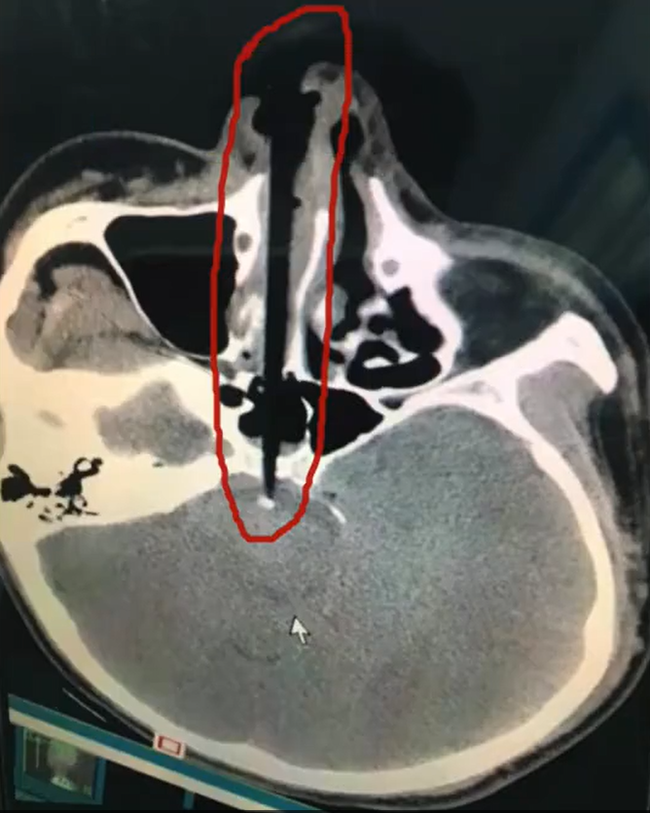

Sau bữa ăn, 1 nam thanh niên tại Trung Quốc đã 'nhanh trí' lấy đũa để ngoáy mũi. Khi đứng dậy, anh bất ngờ vấp ngã và tạo lực đẩy cho cây đũa 20 cm đâm vào hốc mũi. Trải qua ca phẫu thuật và lấy chiếc đũa ra thành công, anh đang dần phục hồi và chờ ngày xuất viện

Theo trang Shanghaiist, một người đàn ông sống ở Hồ Nam, Trung Quốc cảm thấy ngứa ngáy trong lỗ mũi sau khi ăn tối với gia đình. Ngay khi mọi người đứng dậy rời khỏi bàn, không thể chịu đựng được cơn ngứa, anh ta đã với lấy chiếc đũa và làm điều không tưởng: Nhét cây đũa và lỗ mũi và bắt đầu ngoáy mũi không ngừng.

Nhưng điều tồi tệ nhất không phải là chiếc đũa đó vừa để ăn cơm mà lại dùng để ngoáy mũi. Khi anh ta đứng dậy, bỗng bị vấp ngã và mặt cắm xuống đất. Như mọi người có thể tưởng tượng, chiếc đũa 20cm đã cắm thẳng vào hốc mũi. Khi mọi người nghe thấy tiếng kêu thất thanh và quay trở lại phòng ăn, ai nấy đều hãi hùng trước cảnh tượng trước mắt.

Ngay lập tức, anh ta được đưa đến bệnh viện gần nhất, các bác sĩ tiến hành phẫu thuật cấp cứu vì sợ rằng bất kỳ chuyển động nhỏ nào cũng có thể khiến chiếc đũa đẩy sâu vào bên trong hộp sọ.

May mắn là ca phẫu thuật thành công, người đàn ông này hiện đang phục hồi tích cực và sớm ra viện